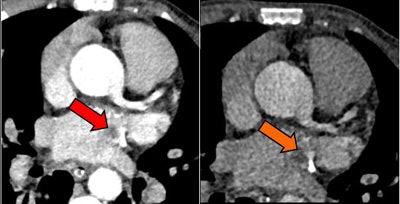

Above, an adult with a left atrial thrombus that was unreported on echocardiography and seen on CT as a filling defect on the arterial (red arrow) and delayed (orange arrow) enhancement phases. Below, an adult with remote inferior myocardial infarction that was unreported on echocardiography and seen on CT as left ventricular inferior myocardial thinning (red arrow). All images courtesy of Dr. Amr Ajlan.Scanning for cardioembolic stroke